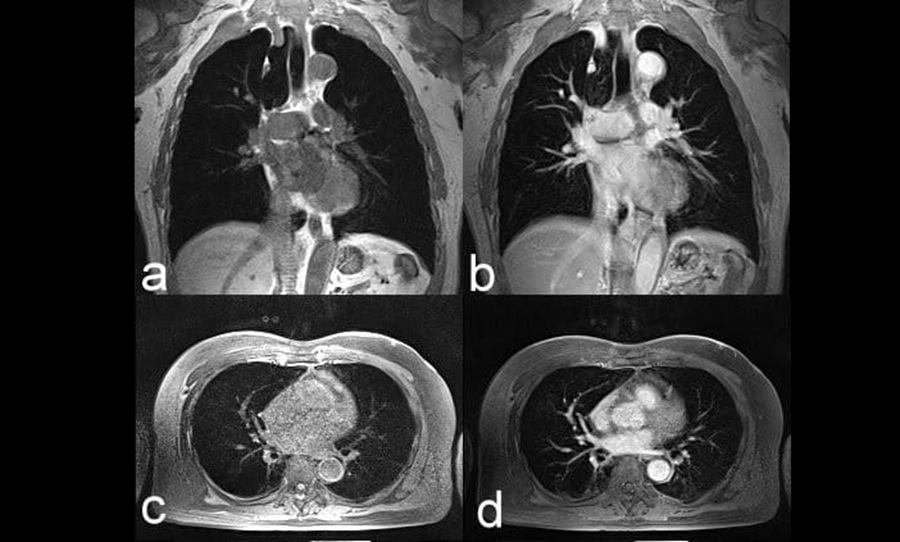

Магнитно-резонансная томография даёт возможность визуализировать не только лёгочную ткань, но и прилегающие структуры, что делает её особенно полезной при диагностике сложных случаев. С её помощью можно обнаружить опухоли, определить их точные границы и степень вовлечения соседних органов. Также МРТ позволяет выявить воспалительные процессы, участки фиброза, жидкости в плевральной полости, аномальные утолщения плевры и поражения лимфоузлов. Аппарат передаёт чёткое изображение мягких тканей, сосудистых разветвлений и бронхиального дерева, что важно при комплексной оценке состояния пациента.

Одно из преимуществ метода – возможность отличить старые рубцовые изменения от активного воспаления или опухолевого роста. Это особенно ценно в онкологической практике, где необходимо точное понимание степени распространённости процесса. Также МРТ может помочь при оценке постоперационных осложнений, таких как инфильтраты, гематомы или послеоперационные изменения в грудной полости. Для врачей важно видеть не только наличие изменений, но и их структуру: плотность, сигнал на разных режимах, границы и связь с окружающими тканями – всё это предоставляет именно МРТ.

При использовании контрастного усиления МРТ лёгких позволяет значительно расширить возможности визуализации: становится возможным более точно оценить кровоснабжение патологических очагов, отличить злокачественные новообразования от доброкачественных и проследить, как организм отвечает на лечение. Этот метод особенно полезен для мониторинга воспалительных изменений у пациентов, которым нежелательно часто проходить КТ. В результате МРТ выступает не как замена другим методам, а как самостоятельный инструмент, обладающий рядом специфических преимуществ при исследовании органов грудной клетки.

Наибольшую информативность МРТ показывает при исследовании мягкотканевых структур, расположенных рядом с лёгкими. Это плевра, бронхи, сосуды, лимфоузлы, диафрагма и элементы средостения. В некоторых случаях удаётся визуализировать даже крупные участки патологии в лёгочной ткани – инфильтраты, фиброз, участки ателектаза, особенно если они граничат с плеврой или сосудами. Аппараты высокого поля (1.5Т и 3Т) дают более чёткие изображения и применяются в сложных диагностических ситуациях, когда необходимо оценить не только саму лёгочную ткань, но и реакцию окружающих структур.